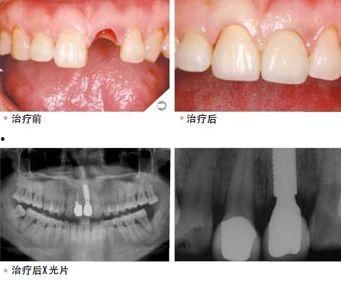

牙周病是导致牙齿脱落的主要原因之一。这种病会导致牙齿周围的牙龈发炎、萎缩,最终导致牙齿松动,甚至脱落。据统计,我国成年人牙周病的患病率高达70%以上。

牙齿松动也是导致牙齿脱落的重要原因。牙齿松动可能是由于牙周病、牙齿受到撞击等原因造成的。当牙齿松动到一定程度时,就很容易脱落。

牙齿脱落对人们的生活影响很大。一方面,牙齿脱落会影响人们的咀嚼功能,导致消化不良;另一方面,牙齿脱落还会影响人们的社交和心理健康。

牙齿脱落会导致咀嚼功能受损,使得食物难以消化吸收。长期下去,可能会导致营养不良、身体虚弱等问题。

牙齿脱落还会影响人们的社交和心理健康。比如,有些人因为牙齿脱落而变得自卑、不敢与人交往。